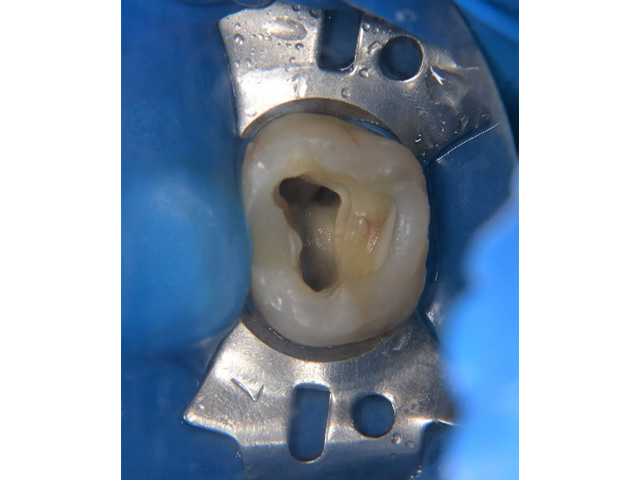

術前(主訴は左上の奥歯の歯ぐきの腫れが気になるということでした)

左上の第一大臼歯および第二大臼歯をラバーダムというゴムのマスクを使用して無菌的な環境の中で歯の神経の治療を行いました。

根管治療終了後のレントゲン写真です。

根の先までお薬を詰めることができましたが1か月後歯ぐきの腫れが再発したため患者さまとご相談し意図的再植術を行い感染源の除去を行うことしました。

① 隣の歯に負担をかけないように事前に水色のゴムを入れて歯と歯の間を開きます